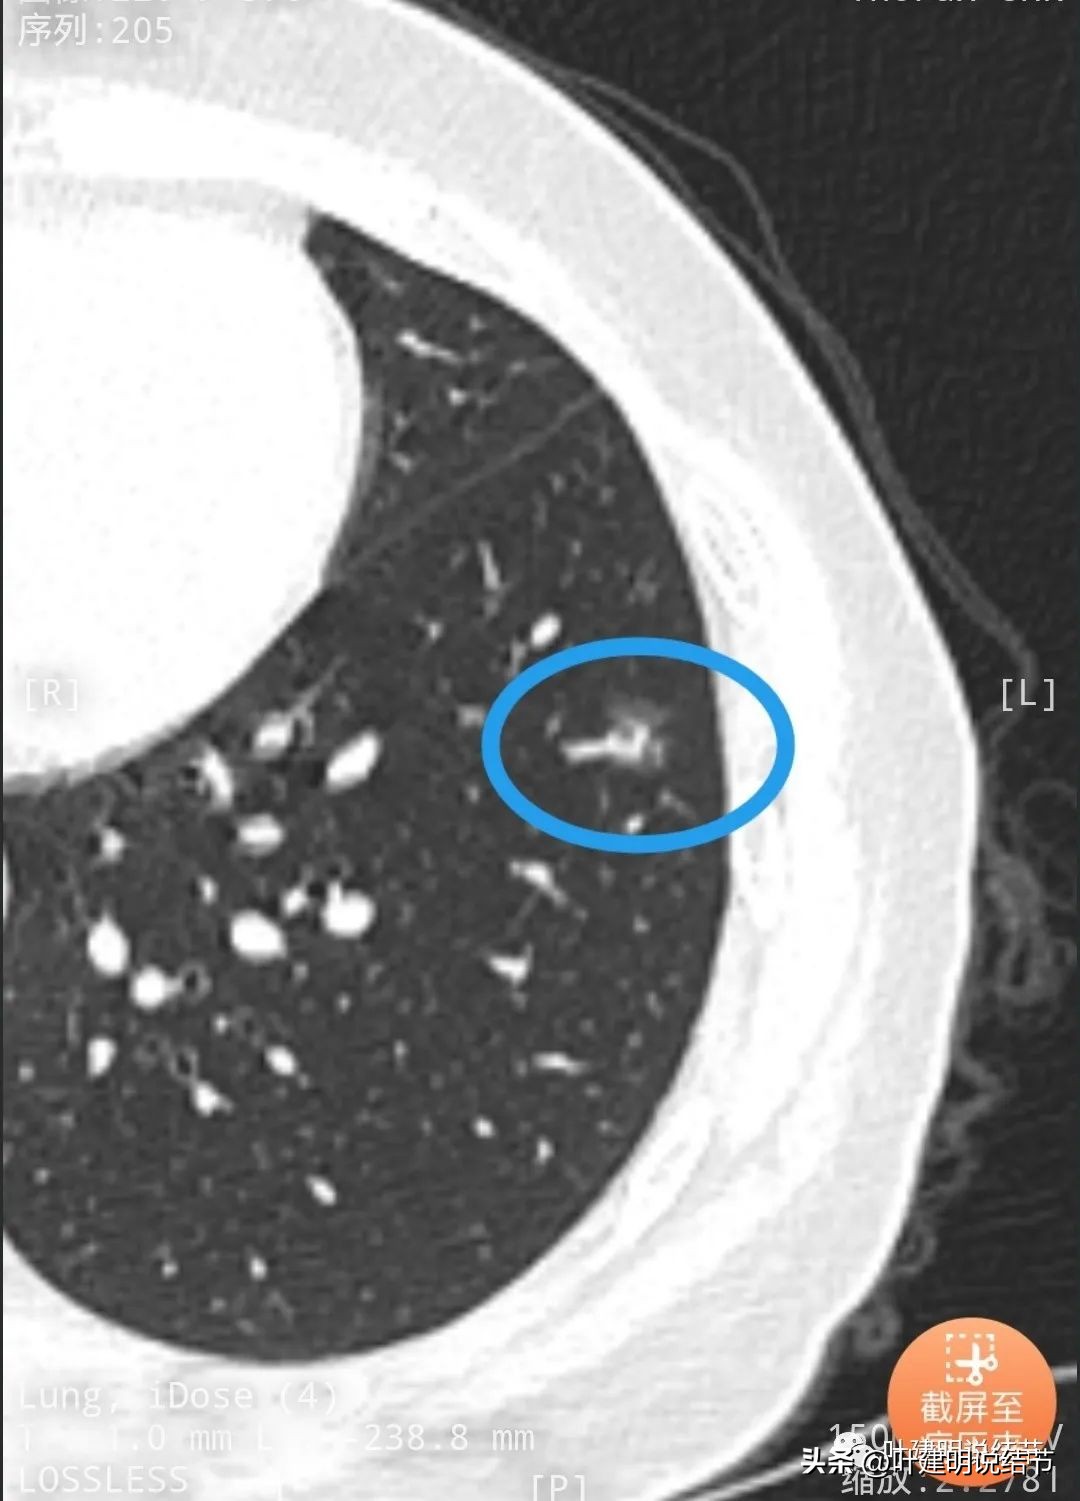

再看左下叶的主病灶,此层见其是磨玻璃密度,轮廓较清,内部密度欠均匀。

有明显血管征,血管进入后有分支发出,病灶表面显得有毛刺样。

病灶中间有空腔。